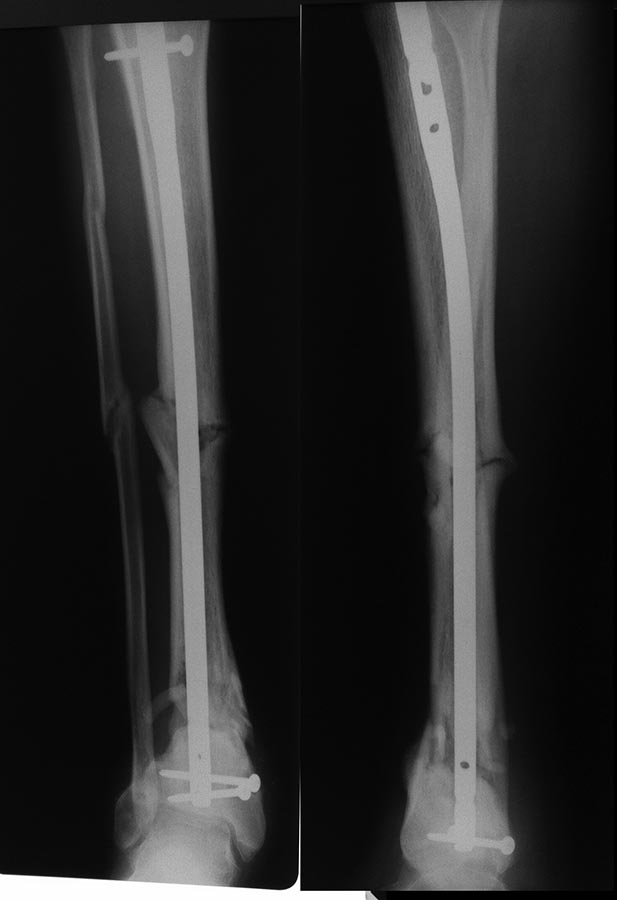

[Ortho] Сегментарный перелом голени в условиях БИОС.

Снимки от мая 2016